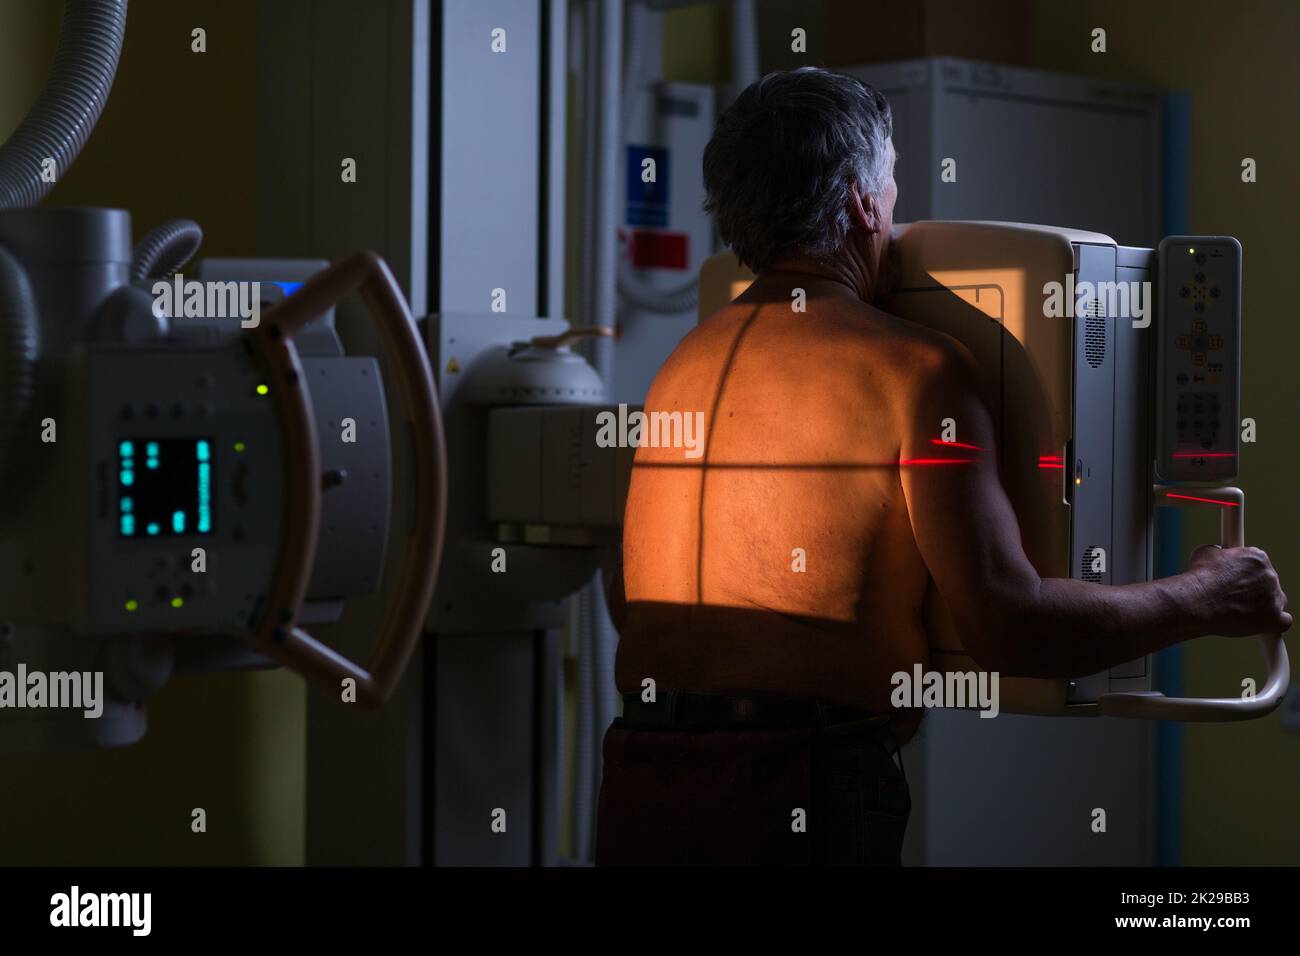

Senior man x-ray medical scan examination in a modern hospital (color toned image) Stock Photohttps://www.alamy.com/image-license-details/?v=1https://www.alamy.com/senior-man-x-ray-medical-scan-examination-in-a-modern-hospital-color-toned-image-image483326106.html

Senior man x-ray medical scan examination in a modern hospital (color toned image) Stock Photohttps://www.alamy.com/image-license-details/?v=1https://www.alamy.com/senior-man-x-ray-medical-scan-examination-in-a-modern-hospital-color-toned-image-image483326106.htmlRF2K29BAJ–Senior man x-ray medical scan examination in a modern hospital (color toned image)

Senior man x-ray medical scan examination in a modern hospital (color toned image) Stock Photohttps://www.alamy.com/image-license-details/?v=1https://www.alamy.com/senior-man-x-ray-medical-scan-examination-in-a-modern-hospital-color-toned-image-image483326111.html

Senior man x-ray medical scan examination in a modern hospital (color toned image) Stock Photohttps://www.alamy.com/image-license-details/?v=1https://www.alamy.com/senior-man-x-ray-medical-scan-examination-in-a-modern-hospital-color-toned-image-image483326111.htmlRF2K29BAR–Senior man x-ray medical scan examination in a modern hospital (color toned image)

Senior man x-ray medical scan examination in a modern hospital (color toned image) Stock Photohttps://www.alamy.com/image-license-details/?v=1https://www.alamy.com/senior-man-x-ray-medical-scan-examination-in-a-modern-hospital-color-toned-image-image483326115.html

Senior man x-ray medical scan examination in a modern hospital (color toned image) Stock Photohttps://www.alamy.com/image-license-details/?v=1https://www.alamy.com/senior-man-x-ray-medical-scan-examination-in-a-modern-hospital-color-toned-image-image483326115.htmlRF2K29BAY–Senior man x-ray medical scan examination in a modern hospital (color toned image)

Senior man x-ray medical scan examination in a modern hospital (color toned image) Stock Photohttps://www.alamy.com/image-license-details/?v=1https://www.alamy.com/senior-man-x-ray-medical-scan-examination-in-a-modern-hospital-color-toned-image-image483326119.html

Senior man x-ray medical scan examination in a modern hospital (color toned image) Stock Photohttps://www.alamy.com/image-license-details/?v=1https://www.alamy.com/senior-man-x-ray-medical-scan-examination-in-a-modern-hospital-color-toned-image-image483326119.htmlRF2K29BB3–Senior man x-ray medical scan examination in a modern hospital (color toned image)